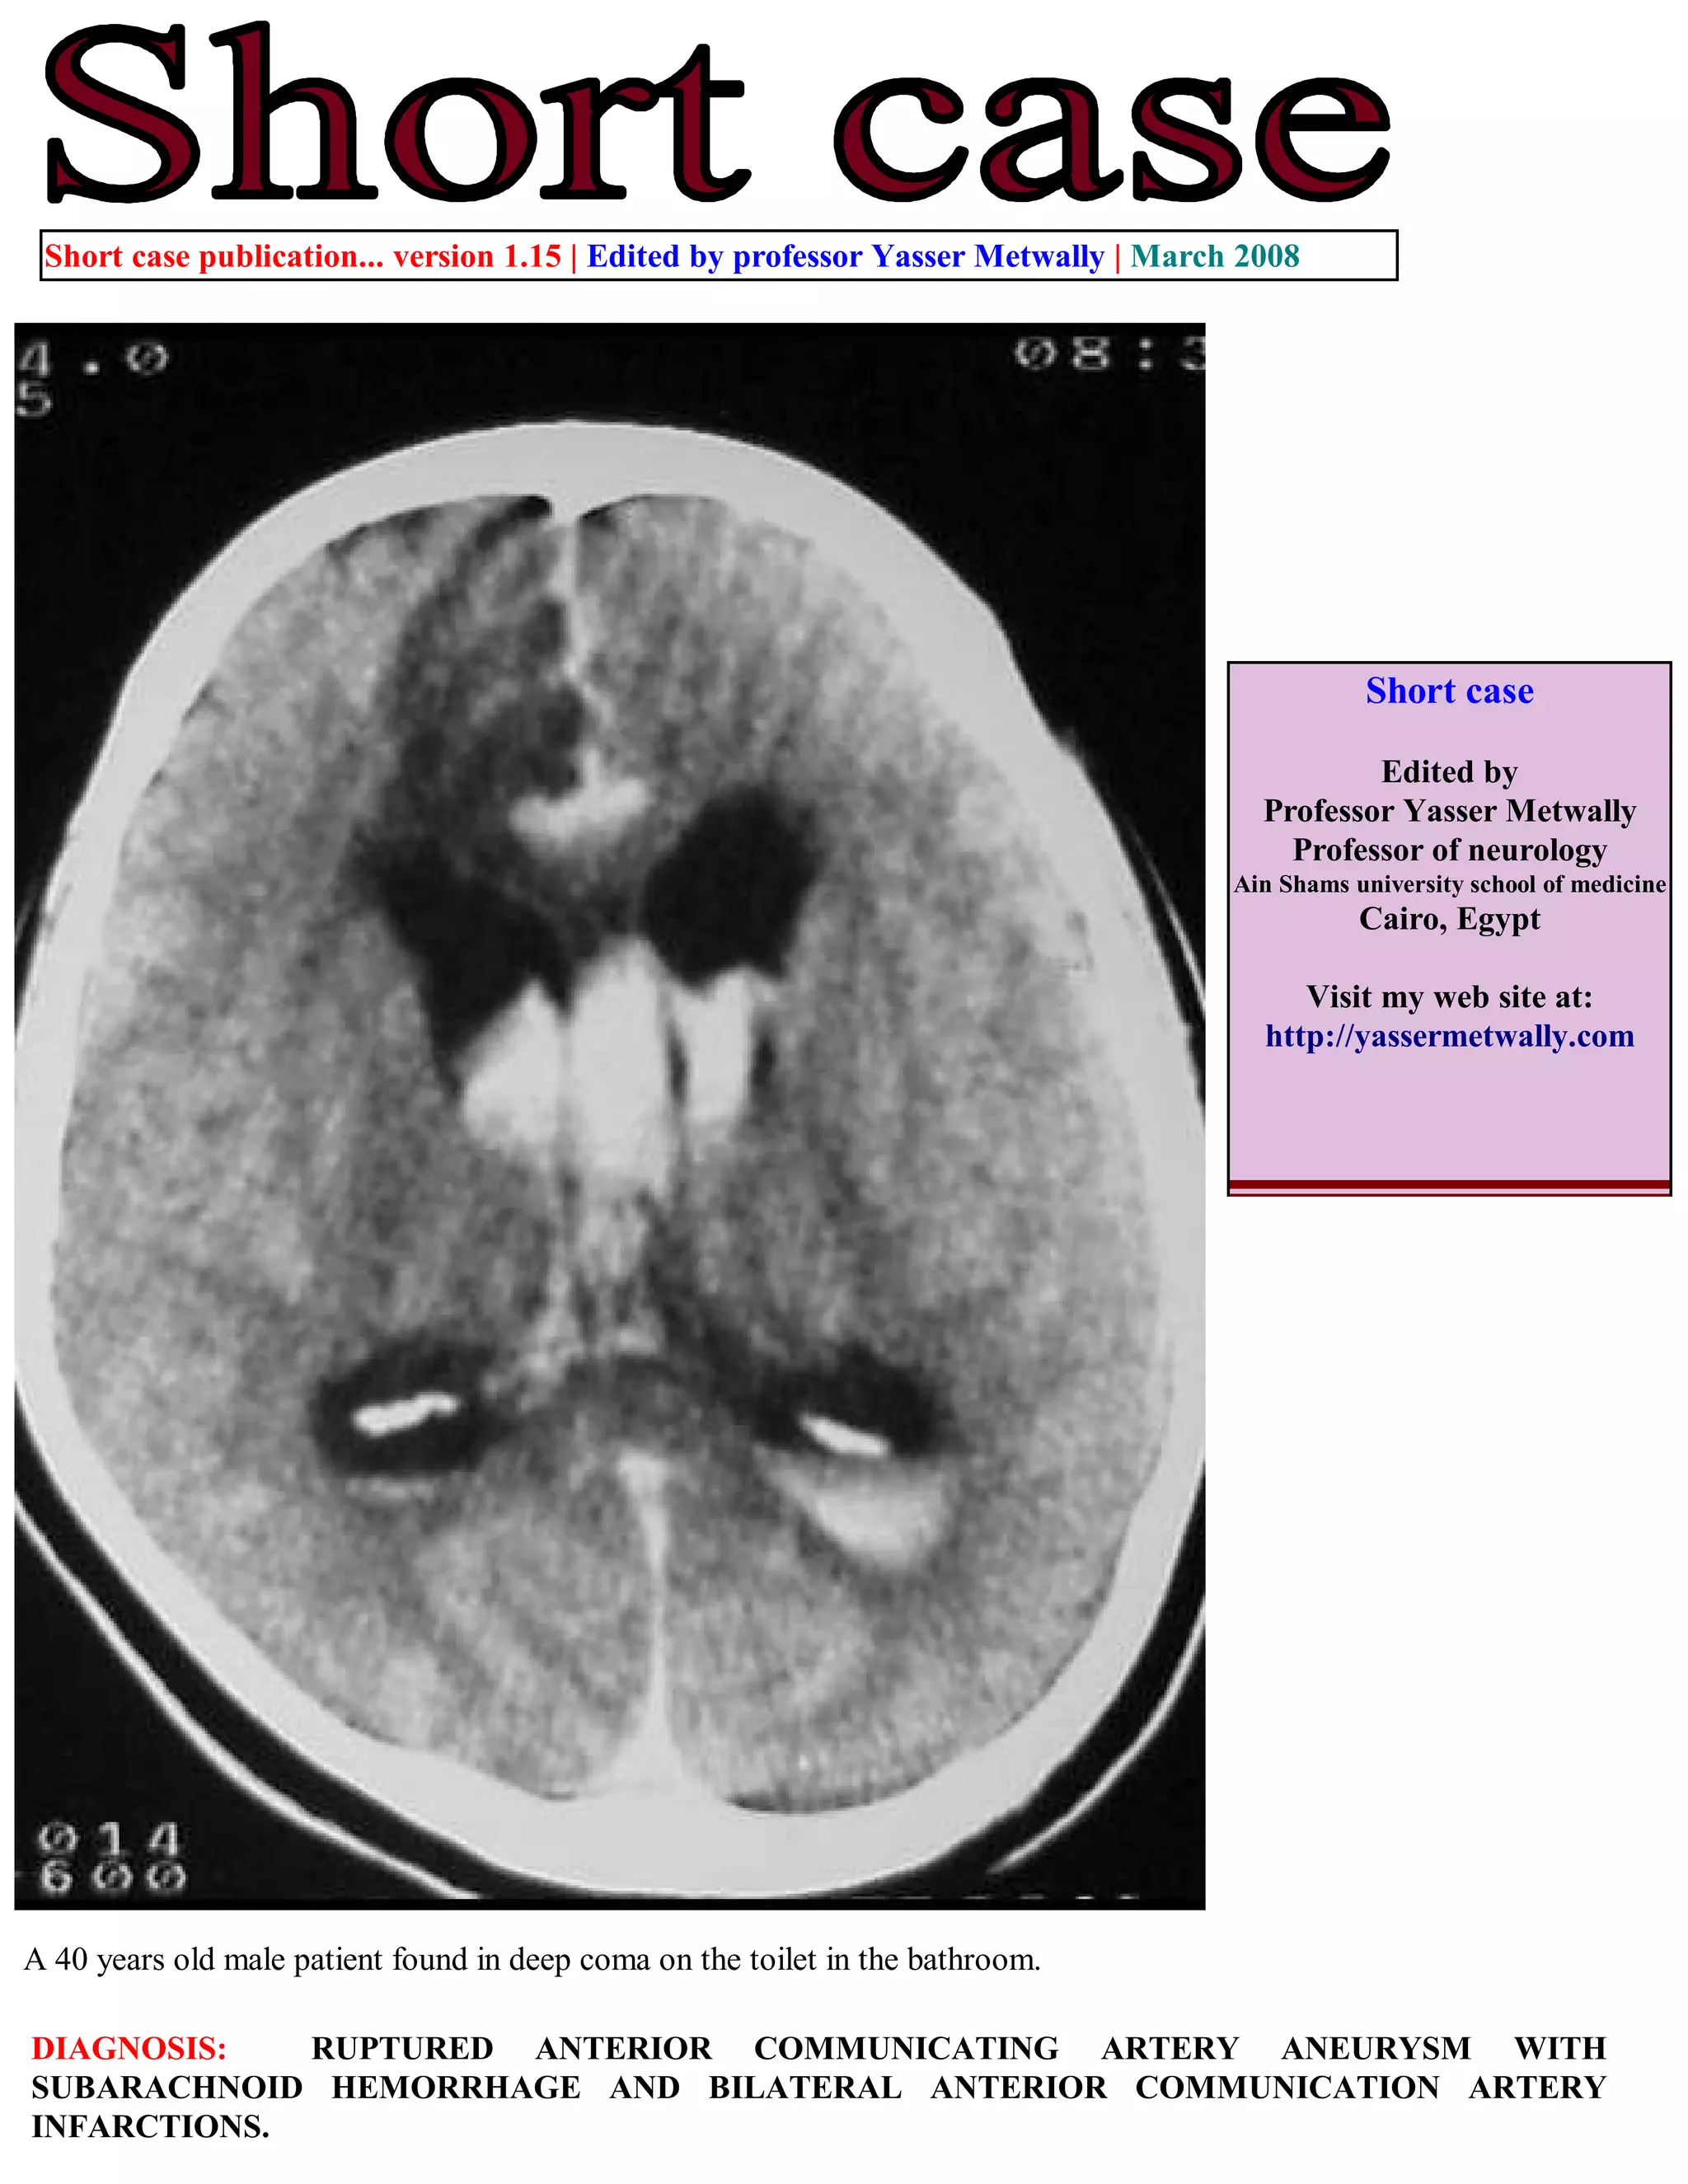

A 40-year-old male patient was found unconscious on a toilet with a ruptured anterior communicating artery aneurysm and subarachnoid hemorrhage. CT scans showed interfrontal subarachnoid hemorrhage breaking into the ventricles with blood in the occipital horns and bilateral anterior cerebral artery infarctions, more severe on the right side. The document describes images of the ruptured anterior communicating artery aneurysm and associated hemorrhaging and edema. It also provides information on accessing updated case publications on the author's website.